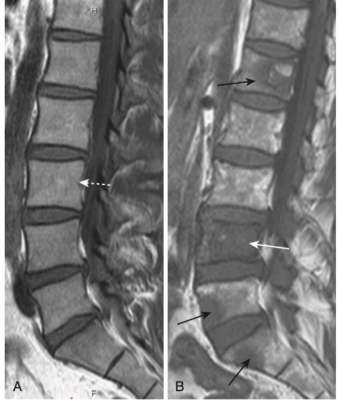

- Khoang tủy hầu như luôn bị ảnh hưởng, từ đó bệnh có thể ăn mòn và phá hủy cả vỏ xương. Khi chỉ ảnh hưởng đến khoang tủy, khối lượng xương phải giảm gần như 50% để có thể nhận biết được tổn thương khi nhìn trực diện trên phim X quang thông thường. Ngược lại, MRI rất hiệu quả trong đánh giá tình trạng của khoang tủy và do đó nhạy hơn nhiều so với chụp X quang thông thường về sự hiện diện của bệnh di căn (Hình 5).

- Ở cột sống, chúng có thể ưu tiên phá hủy các cuống cung, vì nguồn cung cấp máu của cấu trúc này (dấu hiệu ở cuống cung), có thể giúp phân biệt di căn với đa u tủy (bệnh lý này có khuynh hướng không ảnh hưởng đến cuống trong giai đoạn sớm của bệnh (Hình 8).